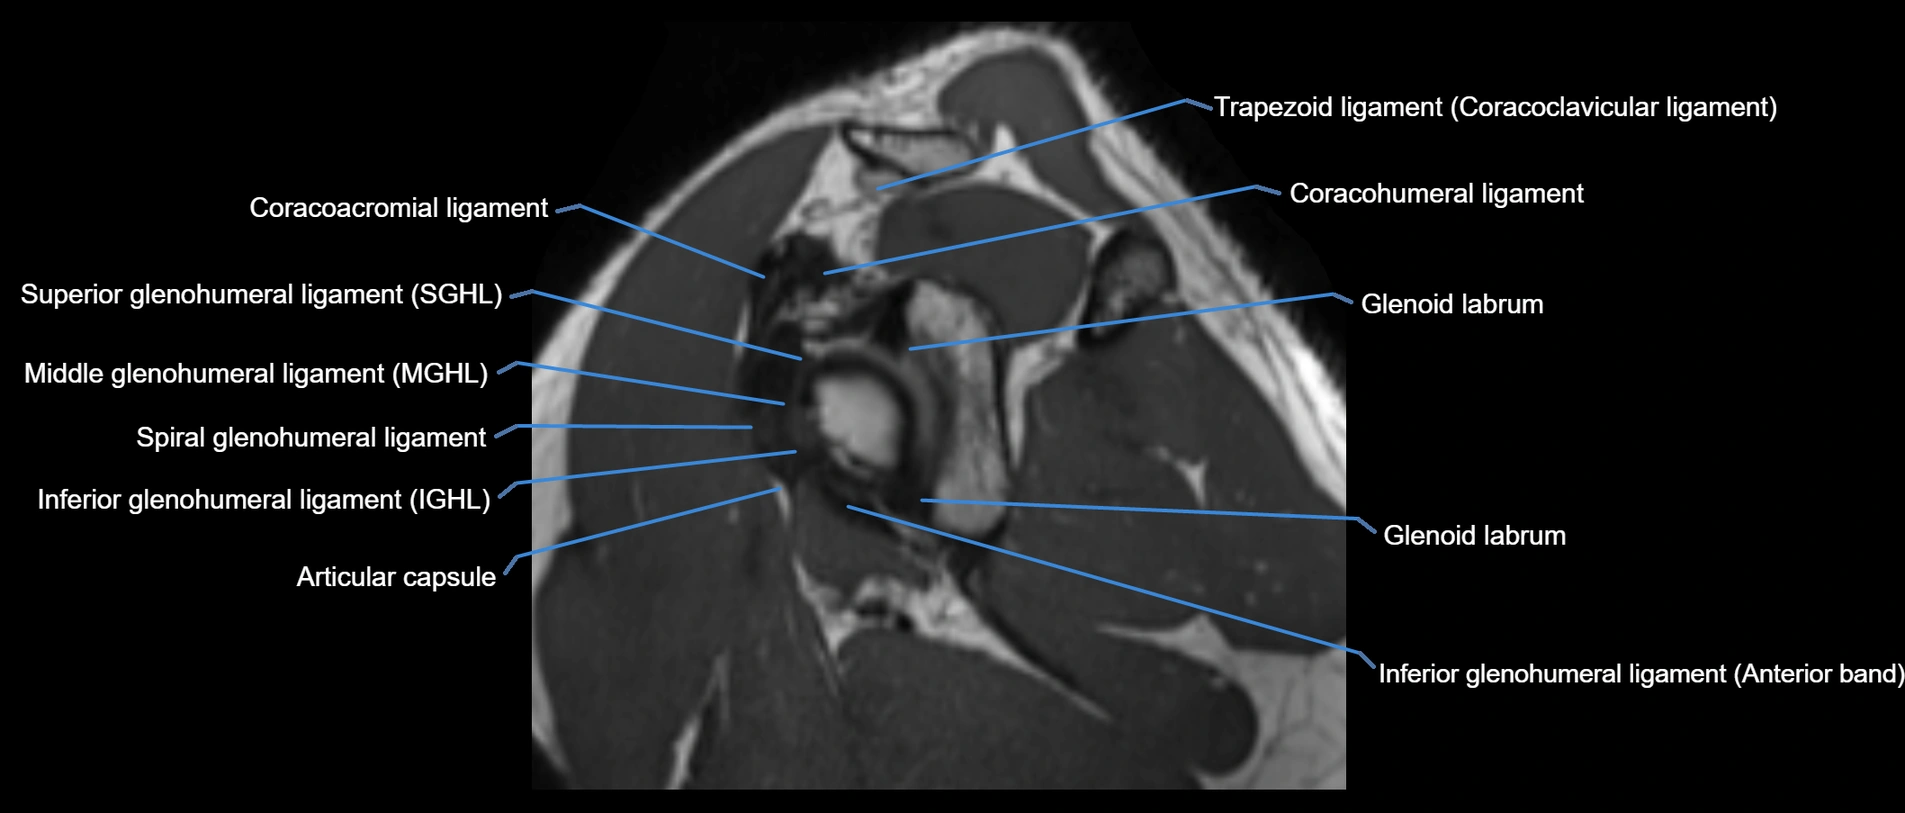

CT image

image